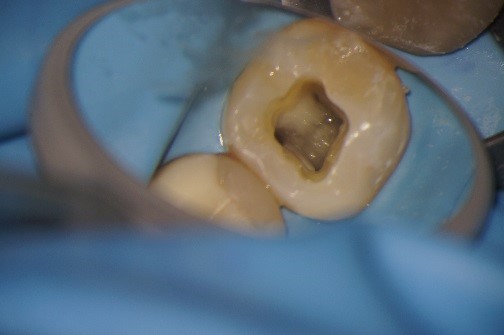

Hieronder ziet u de voortgang van een wortelkanaalbehandeling in zes foto’s..

Foto 1: De kies wordt geopend om de wortelkanaalbehandeling mogelijk te maken.